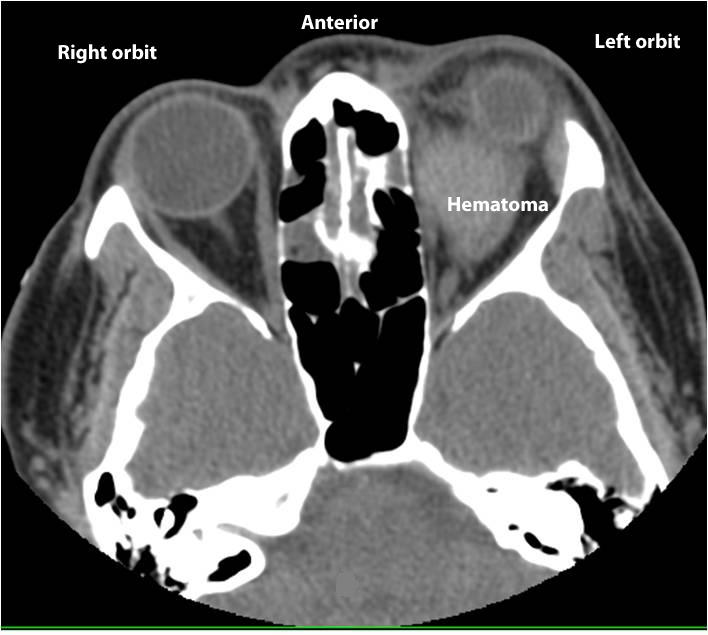

Retrobulbal Hemotoma: Increased bleeding behind the globe can lead to blindness |

![]() |